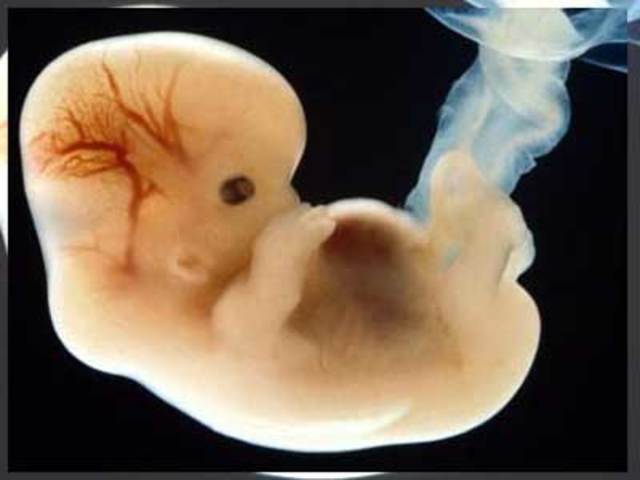

El huevo implantado en la mucosa uterina se divide en dos partes que darán lugar a la placenta y al feto.

Tiene una forma alargada y mide aproximadamente 1,25 mm y presenta un tubo neural, que dará lugar a la formación del sistema nervioso. Tres capas de células formarán la cabeza, el tronco y las extremidades del embrión. Su cuerpo, en forma de coma deja entrever una cabeza y una cola.

En este periodo, su corazón empieza a latir gracias a la fusión de dos vasos sanguíneos.